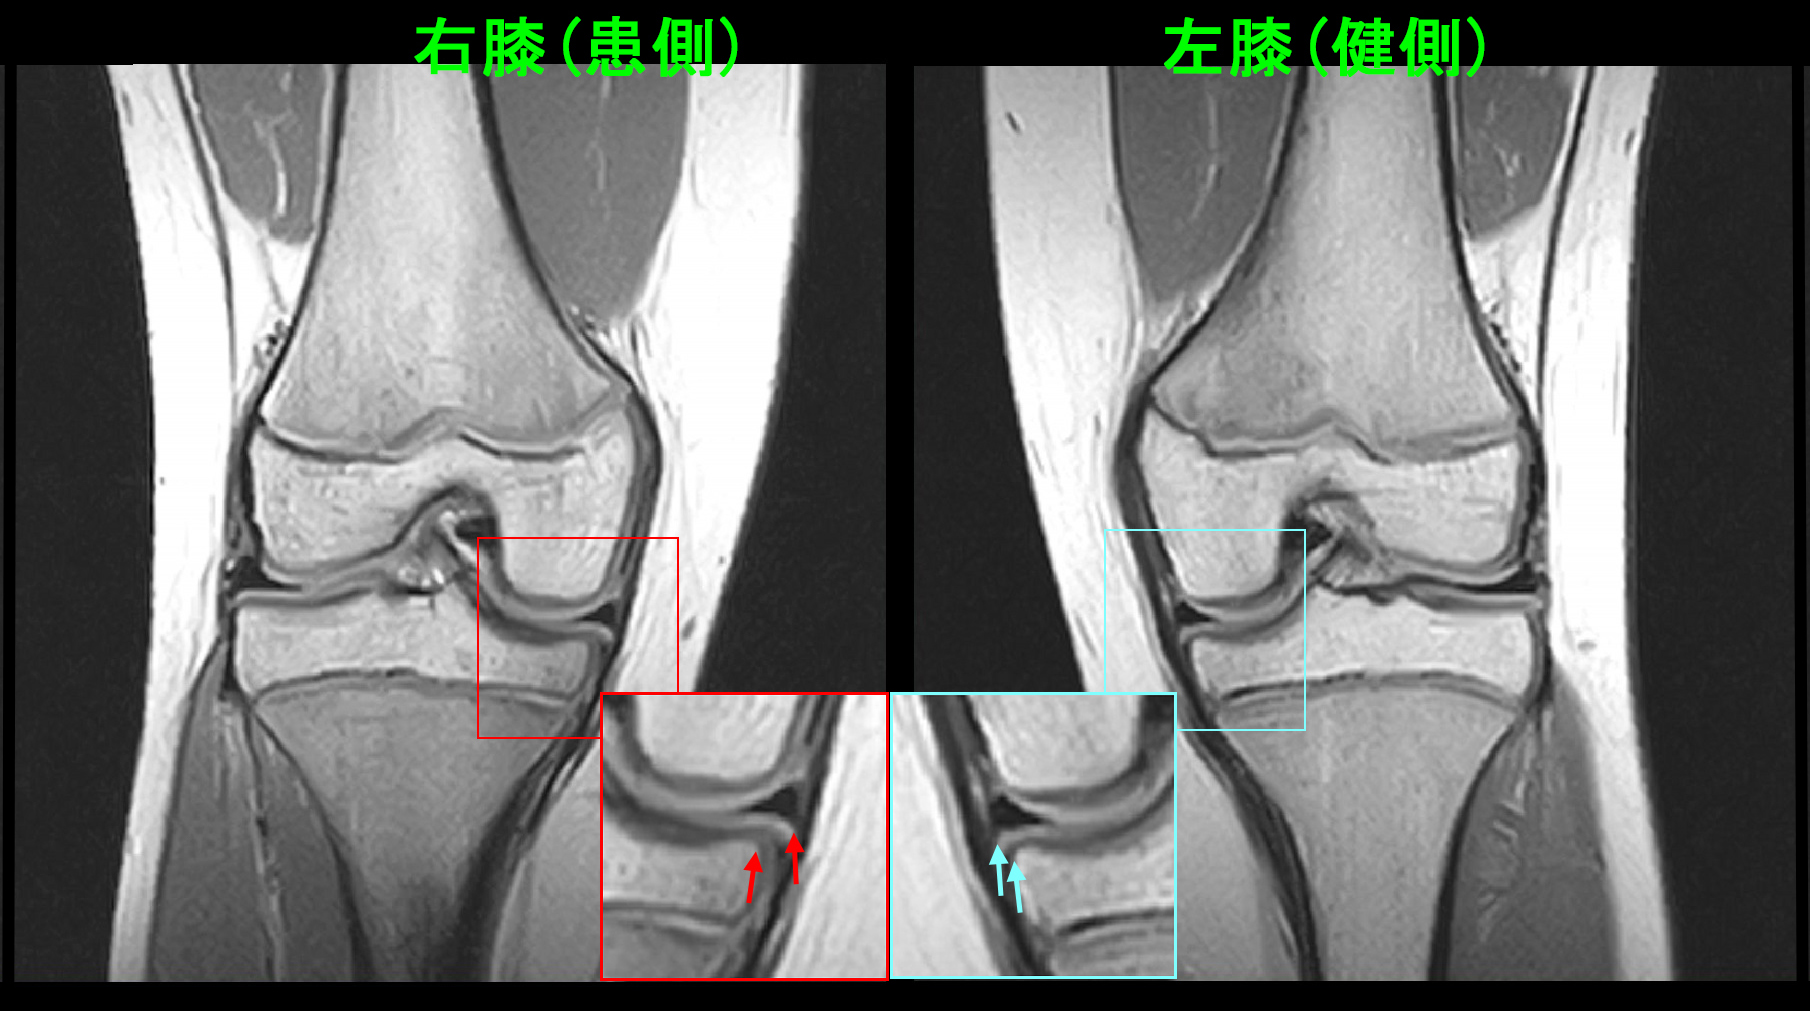

10才女 MR2.jpg

PD冠状断という画像では内側半月板が右では軽度の亜脱臼を示しています。